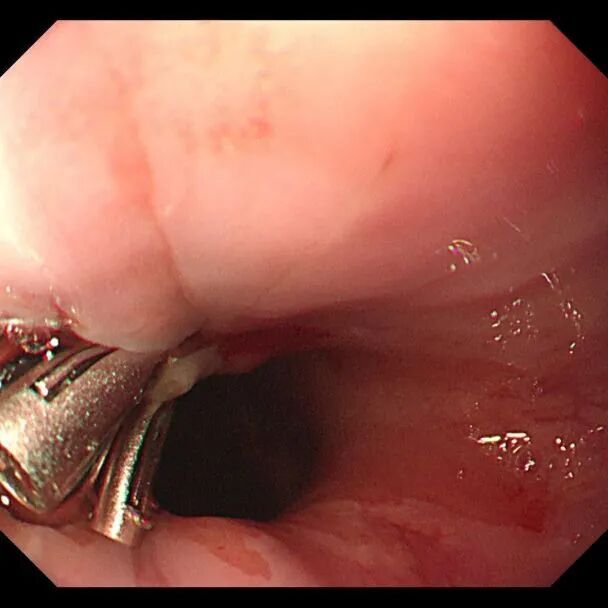

止血后

内镜下止血随即展开,出血被成功控制。术后,患者生命体征趋于平稳,意识清醒,当天下午转入消化科病房继续观察治疗。